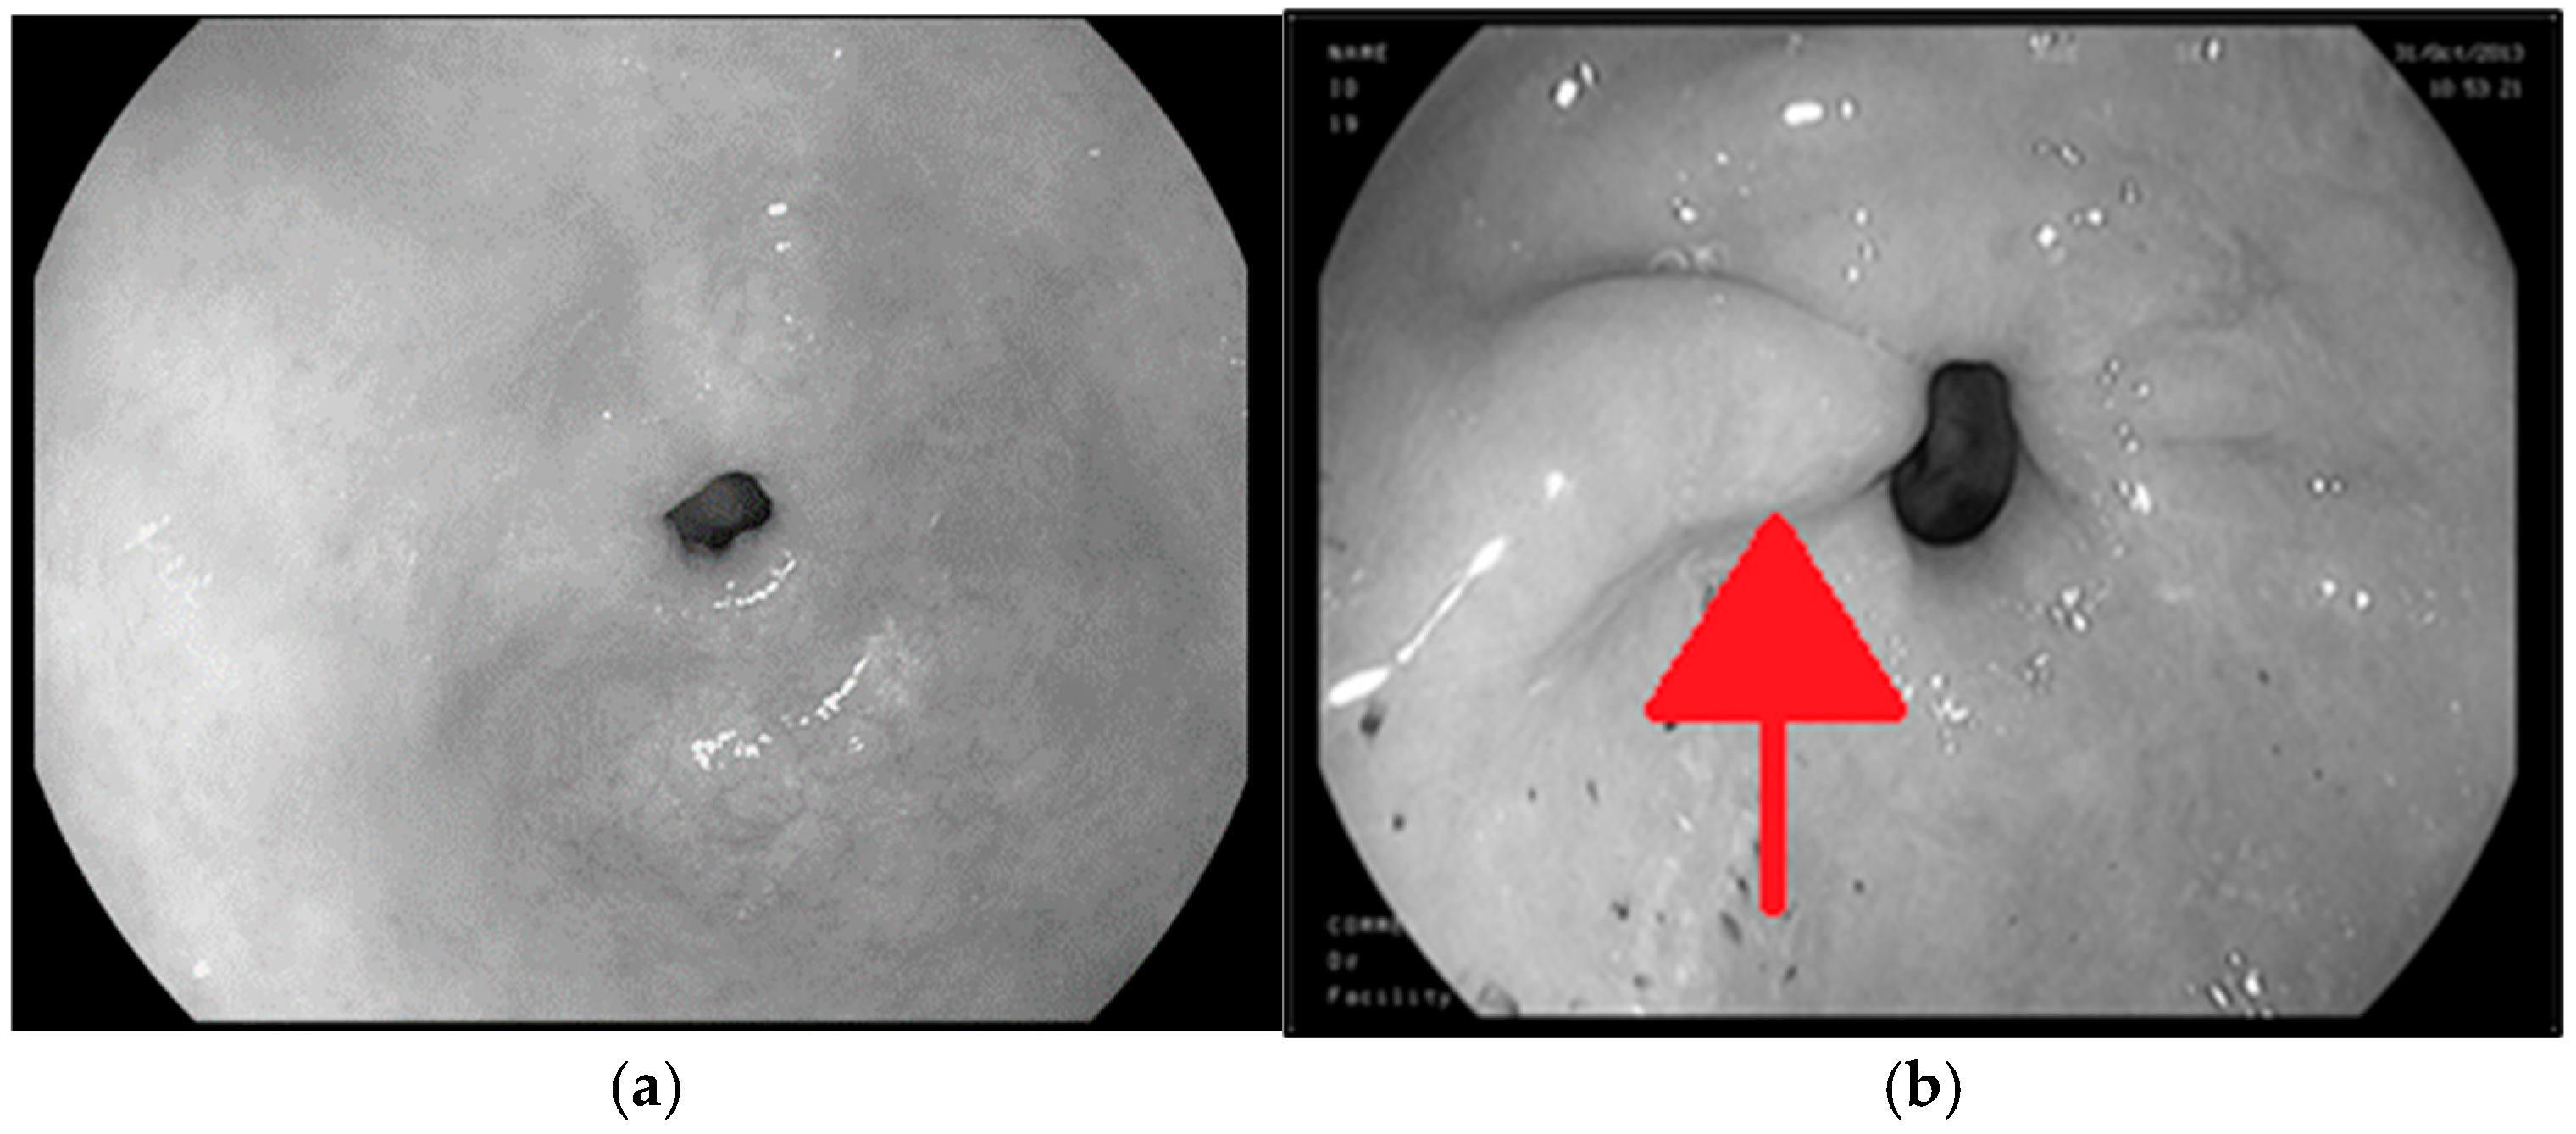

| Case | Dataset | Total Images | Healthy | Polyp | Ulcer |

|---|---|---|---|---|---|

| 3 possible labels | Initial | 1200 | 400 | 400 | 400 |

| Augmented | 4800 | 1600 | 1600 | 1600 | |

| 2 possible labels | Initial | 800 | 400 | 400 | 0 |

| Augmented | 3200 | 1600 | 1600 | 0 |